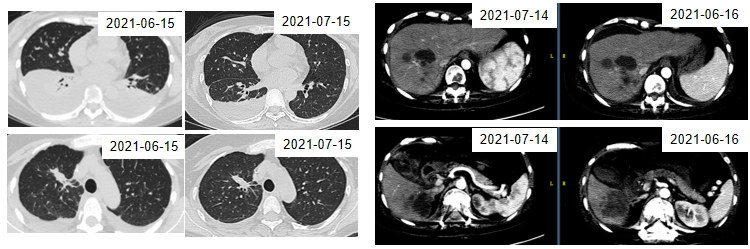

2021年6月15日,患者开始口服伏美替尼(160mg po 1/日)。伏美替尼治疗4周后胸腔积液较前吸收,肝脏转移病灶较前缩小,目前患者仍在持续口服伏美替尼。

图13. 2021年6月与7月的CT检查结果